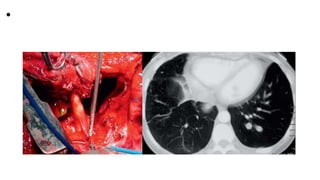

• The patient underwent

thoracotomy and the

findings of numerous

cystic lesions within

the pleura confirming

the diagnosis of

hydatid cysts.